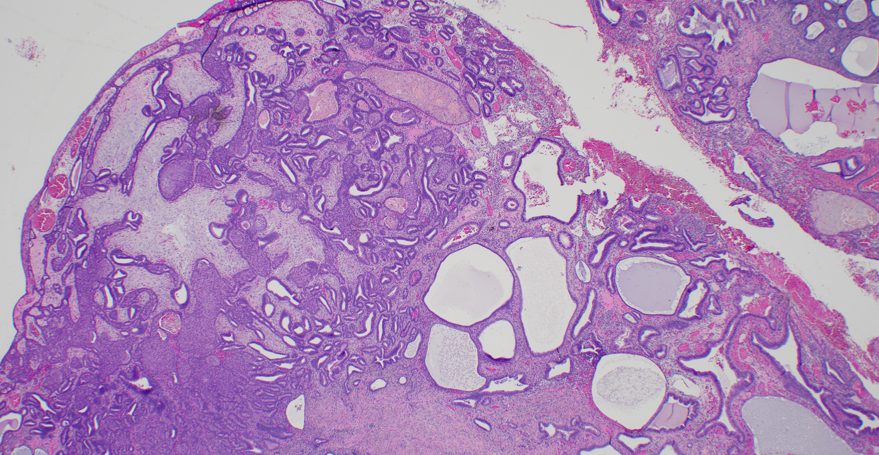

Atypical polypoid adenomyoma: biphasic lesion with crowded, architecturally complex endometrioid glands showing cytologic atypia, embedded in a myomatous stroma. Don’t overcall as carcinoma #PathTwitter #GYNpath